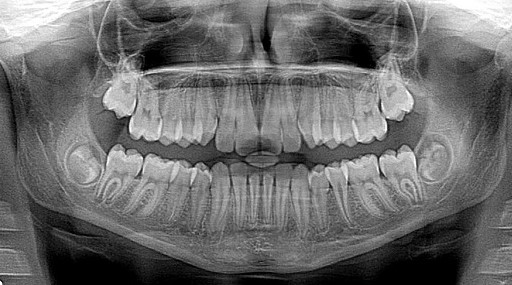

아래턱 사랑니가 신경과 가까운 경우 드물지만 감각 이상이 발생할 수 있습니다. 이를 줄이기 위해 엑스레이나 CT 촬영을 통해 신경과의 거리를 확인하는 것이 좋습니다.

- 엑스레이 촬영을 통해 사랑니 상태를 정확히 확인하기